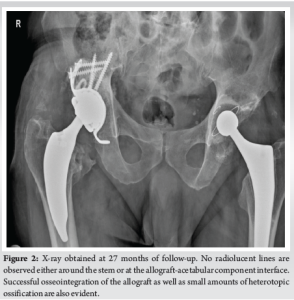

The post-operative course was uneventful and at the final 27 months of follow-up, the patient was free of pain and reported excellent patient-reported outcome measures (PROMs) (Harris Hip Score=93.85, Oxford Hip Score=41, Forgotten Joint Score=86.36, Patient Health Questionnaire-9=0, EQ-5D-5L=0.928, Pain Catastrophizing Scale=2, visual analogue scale=1). No radiolucent lines were observed around the stem as well as around the acetabular component. Moreover, the allograft osseointegration was classified as successful according to the Oswestry radiological classification system [22]. Small amounts of heterotopic ossification were developed in the right hip joint both at the lateral (Brooker 1) and medial side (type 3) [23,24] (Fig. 2).